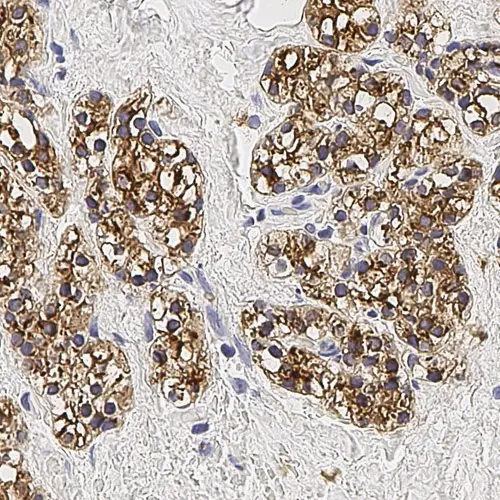

Human high walled venule endothelium and plasmacytoid dendritic cells: immunohistochemical staining for CD123: clone BR4MS

CD123